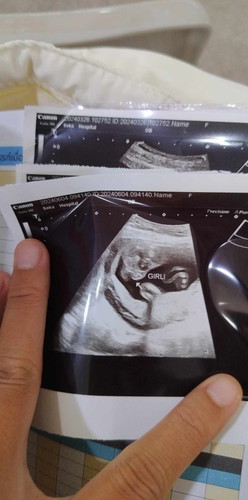

ดูยังไงว่าเป็นหญิงค่ะ

หมอบอกว่าได้ผู้หญิง อันนี้คือส่วนไหนของน้องค่ะ

ตรงลูกศรชี้จ้าเป็นกลีบชัดเจนเลย